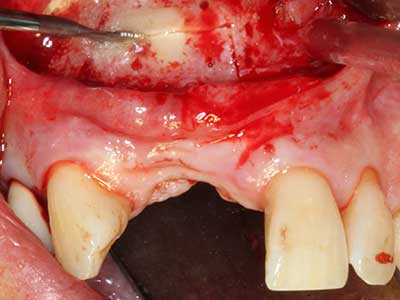

Aplicación: Preparación cerca del nervio

Si es preciso realizar intervenciones quirúrgicas en las que el hueso está en contacto directo con estructuras sensibles, como son los vasos sanguíneos o los nervios, los instrumentos rotativos presentan un enorme potencial de provocar lesiones iatrogénicas. Así, precisamente en la representación de nervios después de una lesión iatrogénica, o en el transcurso de la lateralización de un nervio para resecciones, reconstrucciones o incorporación de implantes, los equipos piezoeléctricos pueden resultar muy útiles para preparar la tapa ósea y retirar las partes de tejido duro cercanas al nervio (fig. 17-20). Por lo general, un ligero contacto del cordón nervioso con el inserto piezoeléctrico no tiene consecuencia alguna; ahora bien, un procedimiento poco cuidadoso con movimientos tipo sierra o piezas de trabajo sobre la base ósea aún existente puede provocar lesiones nerviosas temporales o incluso permanentes. Con todo, el riesgo de sufrir una lesión de este tipo se considera significativamente inferior que en los casos en los que se utilizan sierras y fresas (Pereira, Gealh et al. 2014).